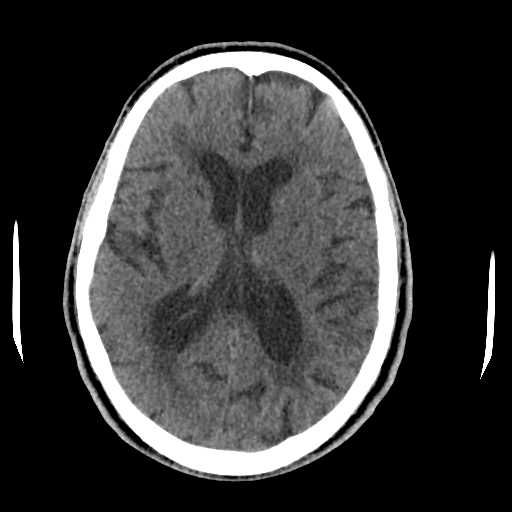

(a) CT scan of a normal brain without any signs of hemorrhage.

Figure 2: (a) CT scan of a normal brain without any signs of hemorrhage, (b) CT scan of a brain with ICH, illustrating visible regions of bleeding.